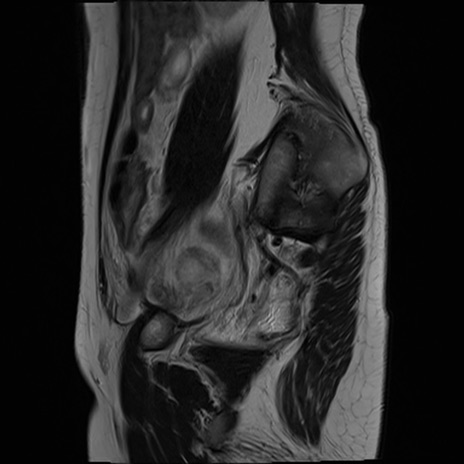

症例39 T2WI(矢状断像)

MRI(4日後)